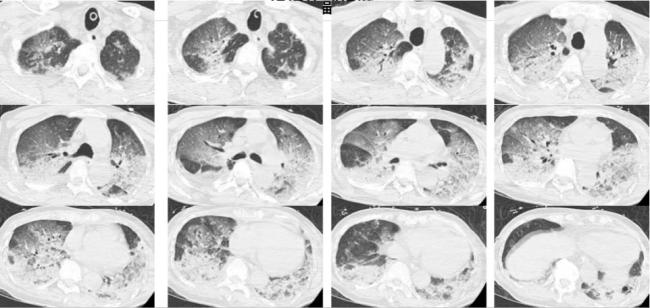

入院時(shí),韓爺爺意識不清,血壓、心率下降,醫(yī)生隨即為他安排頭顱、胸部CT和肺血管CTA檢查,結(jié)果顯示,老人的雙肺出現(xiàn)大面積白色影像。經(jīng)會診,韓爺爺被確診為熱射病誘發(fā)的肺水腫。

冬天也能“中暑”?警惕“冬季熱射病”